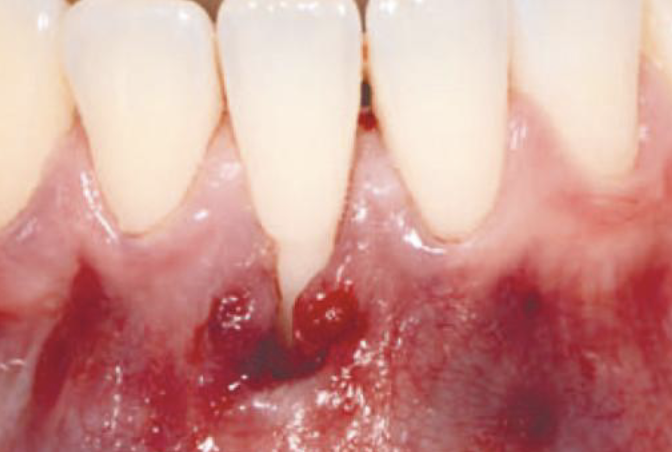

Kliniske kasus med hyaDENT BG Gingival recession (CAF)

Prof. Andrea Pilloni

Pre-operative